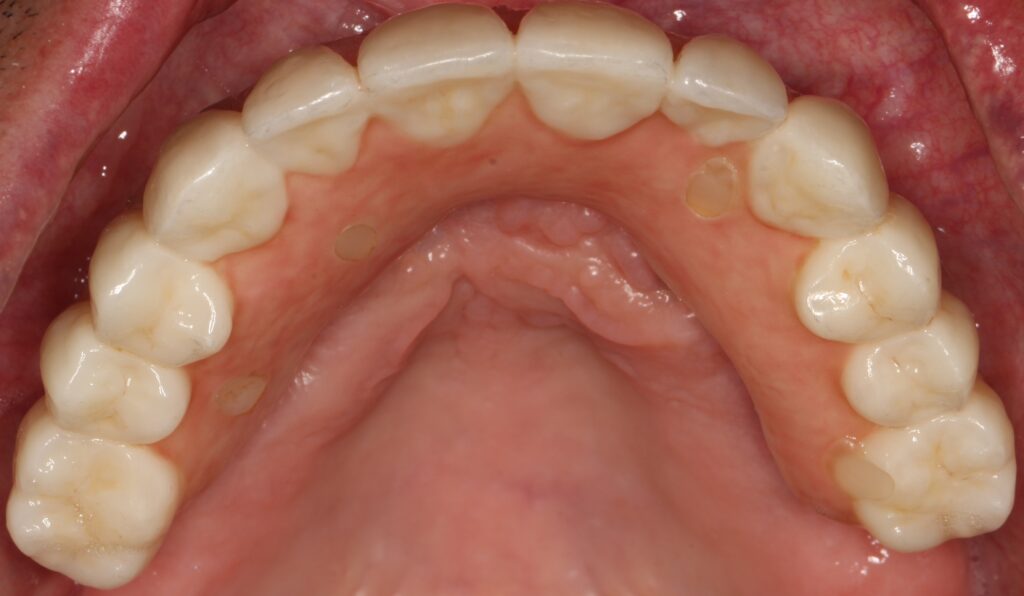

A selection of full arch fixed implant bridge patients after 5 years of wear